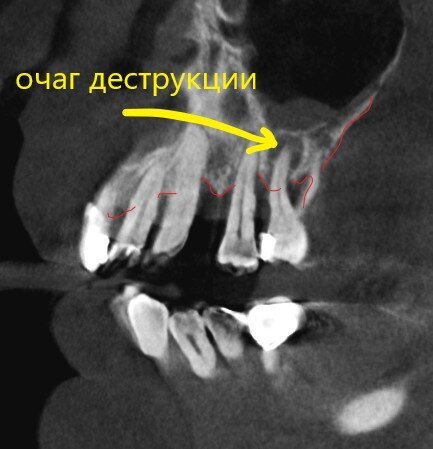

Посмотрим срезы.

Пародонтит.

Зубы цепляются за кость верхушками корней.

Пародонтит.

Куда ни глянь - одна картина.

Пародонтит.

Деструкция кости капитальная.